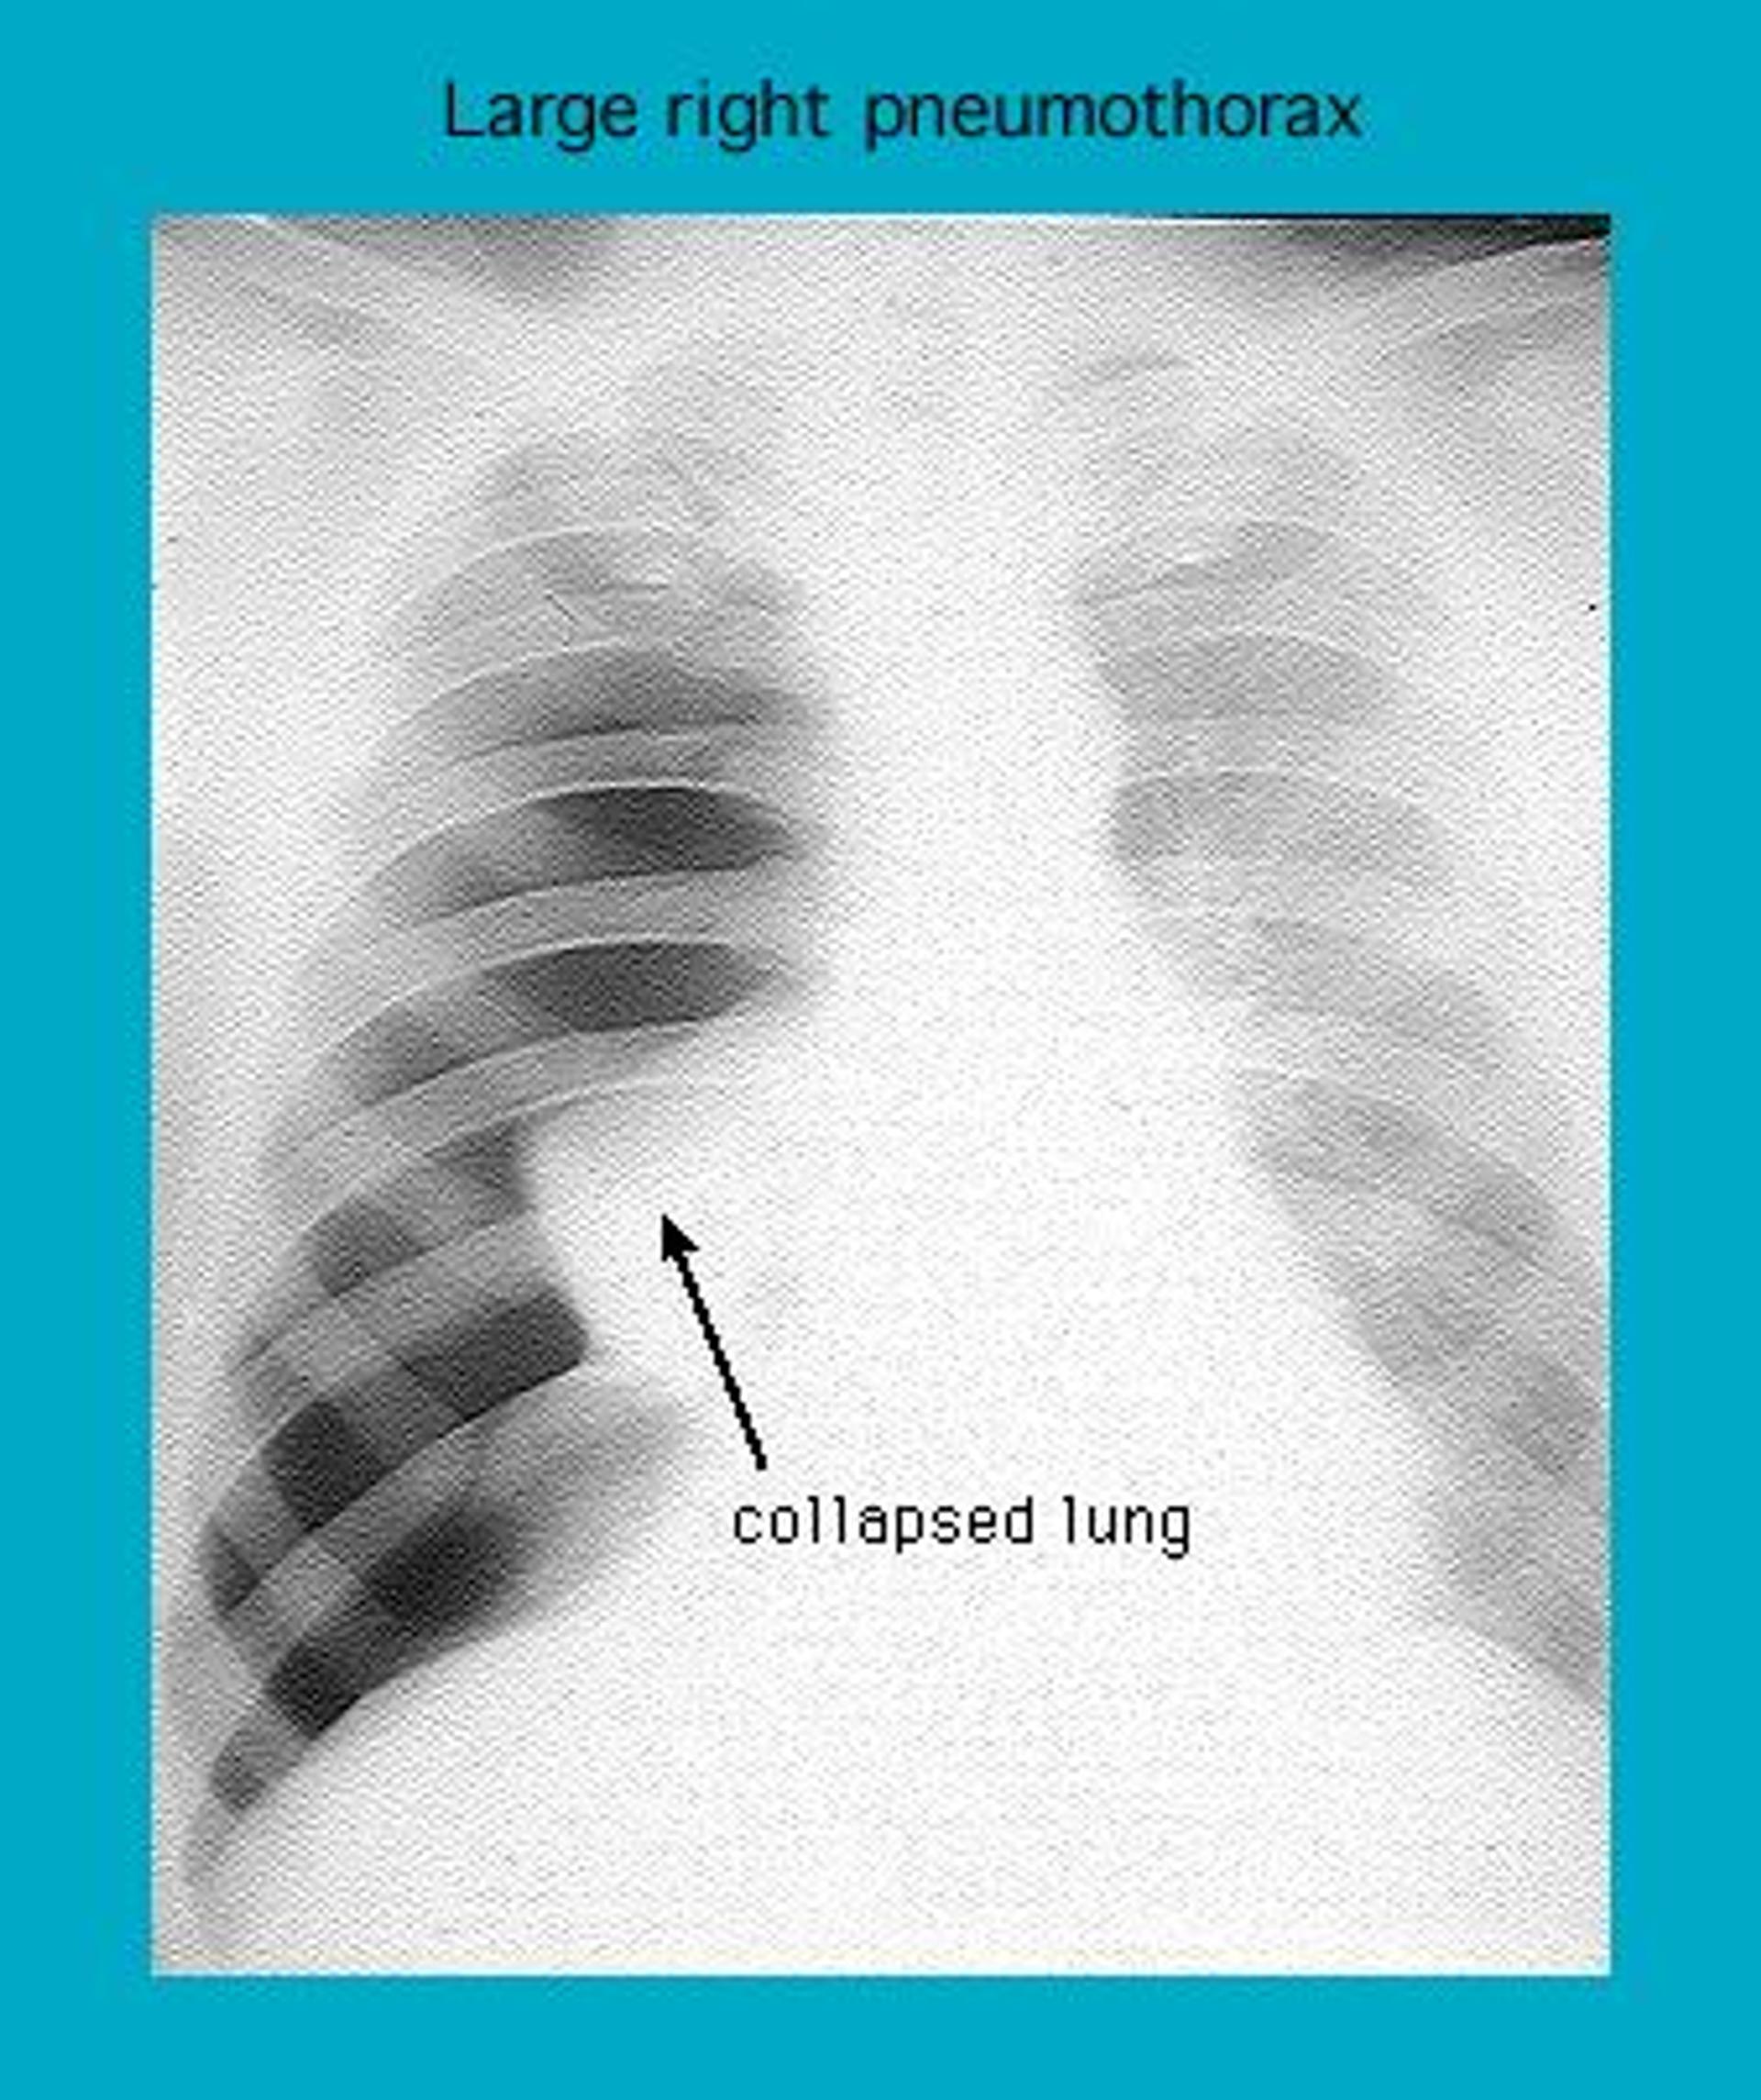

Radiograph showing a right pneumothorax